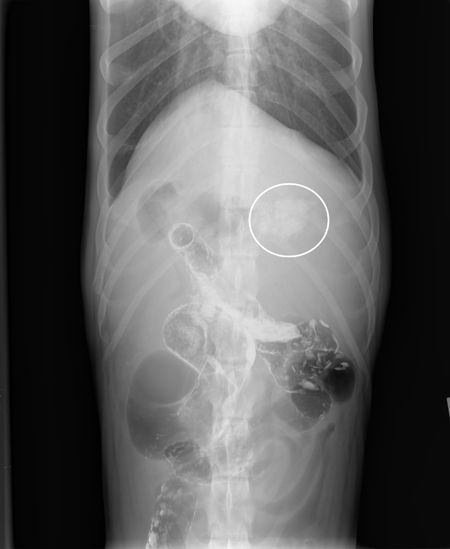

Also, things are hidden on the down side that you can't usually see until you flip the patient over to allow gas in the region to provide radiographic contrast with the soft tissue and fluid that may be present, especially in the abdomen. For example, in most dogs linear foreign bodies get caught in the pylorus of the stomach. A right lateral radiograph puts that side down so it's surrounded by fluid. Therefore the soft tissue of the foreign body blends with the fluid in the stomach and you can't see the lesion. If you're worried about a linear foreign body, take a left lateral radiograph to put gas in the pylorus, allowing you to see the foreign body (Figure 1).

Figure 1A: This left lateral radiograph shows a foreign body (sock) within the pylorus of the stomach and the descending duodenum. Note that you can barely see the linear striations of the lesion on the right lateral radiograph (Figure 1B), but it is clearly seen on the left lateral when gas is present in the fundus. (Radiography images courtesy of Dr. Anthony Pease.)

Figure 1B: Right lateral view.

Figure 1C: Ventrodorsal view.